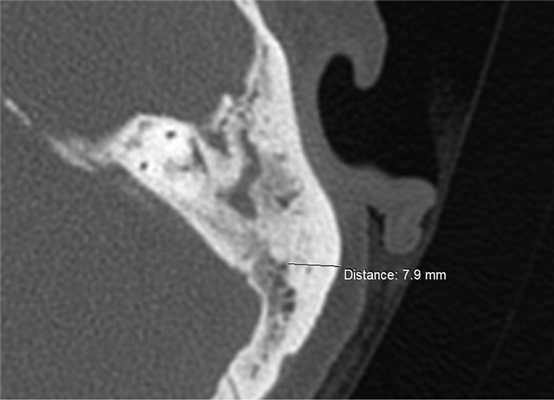

МСКТ височных костей было выполнено перед операцией с целью определения наиболее оптимального участка височной кости для взятия ОТК для облитерации МП при повторных СО на ухе. Также учитывалось положение данного участка по отношению к важным анатомическим структурам (лицевой нерв, сигмовидный синус, горизонтальный полукружный канал, твердая мозговая оболочка средней и задней черепных ямок).

Результаты исследования 60 компьютерных томограмм височных костей больных с ХГСО показали, что наиболее оптимальным участком для взятия стружки аутокости для мастоидопластики является область ВЛ, так как именно в этом месте наружный кортикальный слой кости имеет наибольшую толщину и меньше риск повреждения важных анатомических структур. В среднем толщина наружного кортикального слоя в области височной линии составила 6,4 мм и варьировала от 3,2 мм до 8,3 мм (рис. 2). При толщине наружного кортикального слоя кости менее 4 мм удавалось получить пластический материал только для закрытия глубоких карманов МП. В 6 случаях полученной стружкой аутокости была выполнена полная облитерация М.П. Облитерация М.П. до уровня горизонтального полукружного канала была выполнена у 12 больных. При этом сформирована значительно меньшая по объему послеоперационная полость, что способствовало ее оптимальной эпидермизации. У двух больных вместе с МП был облитерирован эпитимпанум. В 5 случаях удалось взять пластический материал только для облитерации глубоких карманов МП в области верхушки сосцевидного отростка.

Рис. 2. МСКТ левой височной кости, аксиальная проекция. Проекция области височной линии.